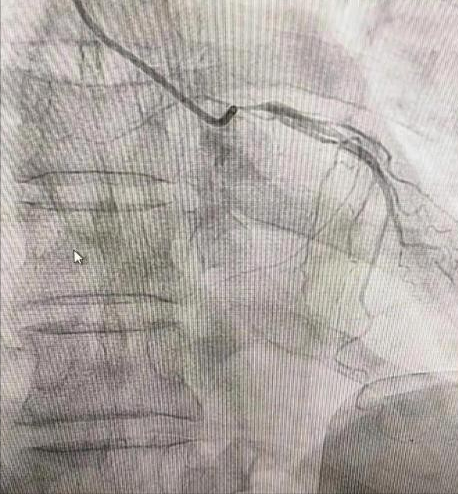

81岁的梁老伯一直身体硬朗,10年前无故出现了胸闷、心前区疼痛的症状。持续数分钟,未治疗。6月19日上述症状加重,伴有一过性意识不清,并伴有恶心呕吐,遂来诊,入院检查后诊断急性非ST抬高型心肌梗死(killip1级),行充分术前检查、冠脉检查后发现,左主干开口99%狭窄,回旋支及右冠状动脉大致正常。

心内科医务人员都知道,像梁老伯这种左主干开口次全闭塞是左主干病变的严重表现之一,病情极度凶险,大部分患者可能没有机会到达医院。有机会到达医院的患者心源性休克发生率达77.8%,及时开通血管能大大降低死亡率,但手术仍存在极大风险,术中任何意外事件或不慎都可能危及生命,且很少有抢救机会,更何况患者已经是81岁的高龄,如若不手术,患者随时都有生命危险。

心内一科医护团队权衡利弊,进行了充分的术前讨论和沟通,明确手术方案,并制定了各种情况的应急抢救处理方案。经过1个小时细致、紧张的操作后,终于开通左主干,并植入2枚支架,恢复患者心肌灌注。手术获得成功。医生表示,术后患者胸痛症状完全缓解,复查各项指标明显好转,几个月后继续复查即可。